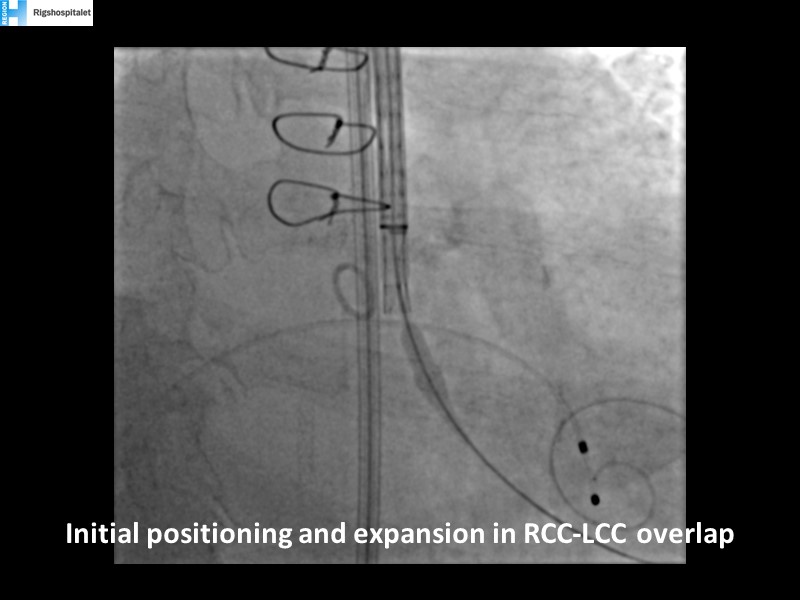

How to deal with challenging anatomies? Find answers in this EuroPCR 2022 session with case studies to explore and learn how to achieve optimal patient outcomes with Evolut platform, uncover practical tips and techniques to achieve implant precision and control, and become familiar with technical considerations and procedural execution of TAVI.

- To uncover practical tips and techniques to achieve implant precision and control